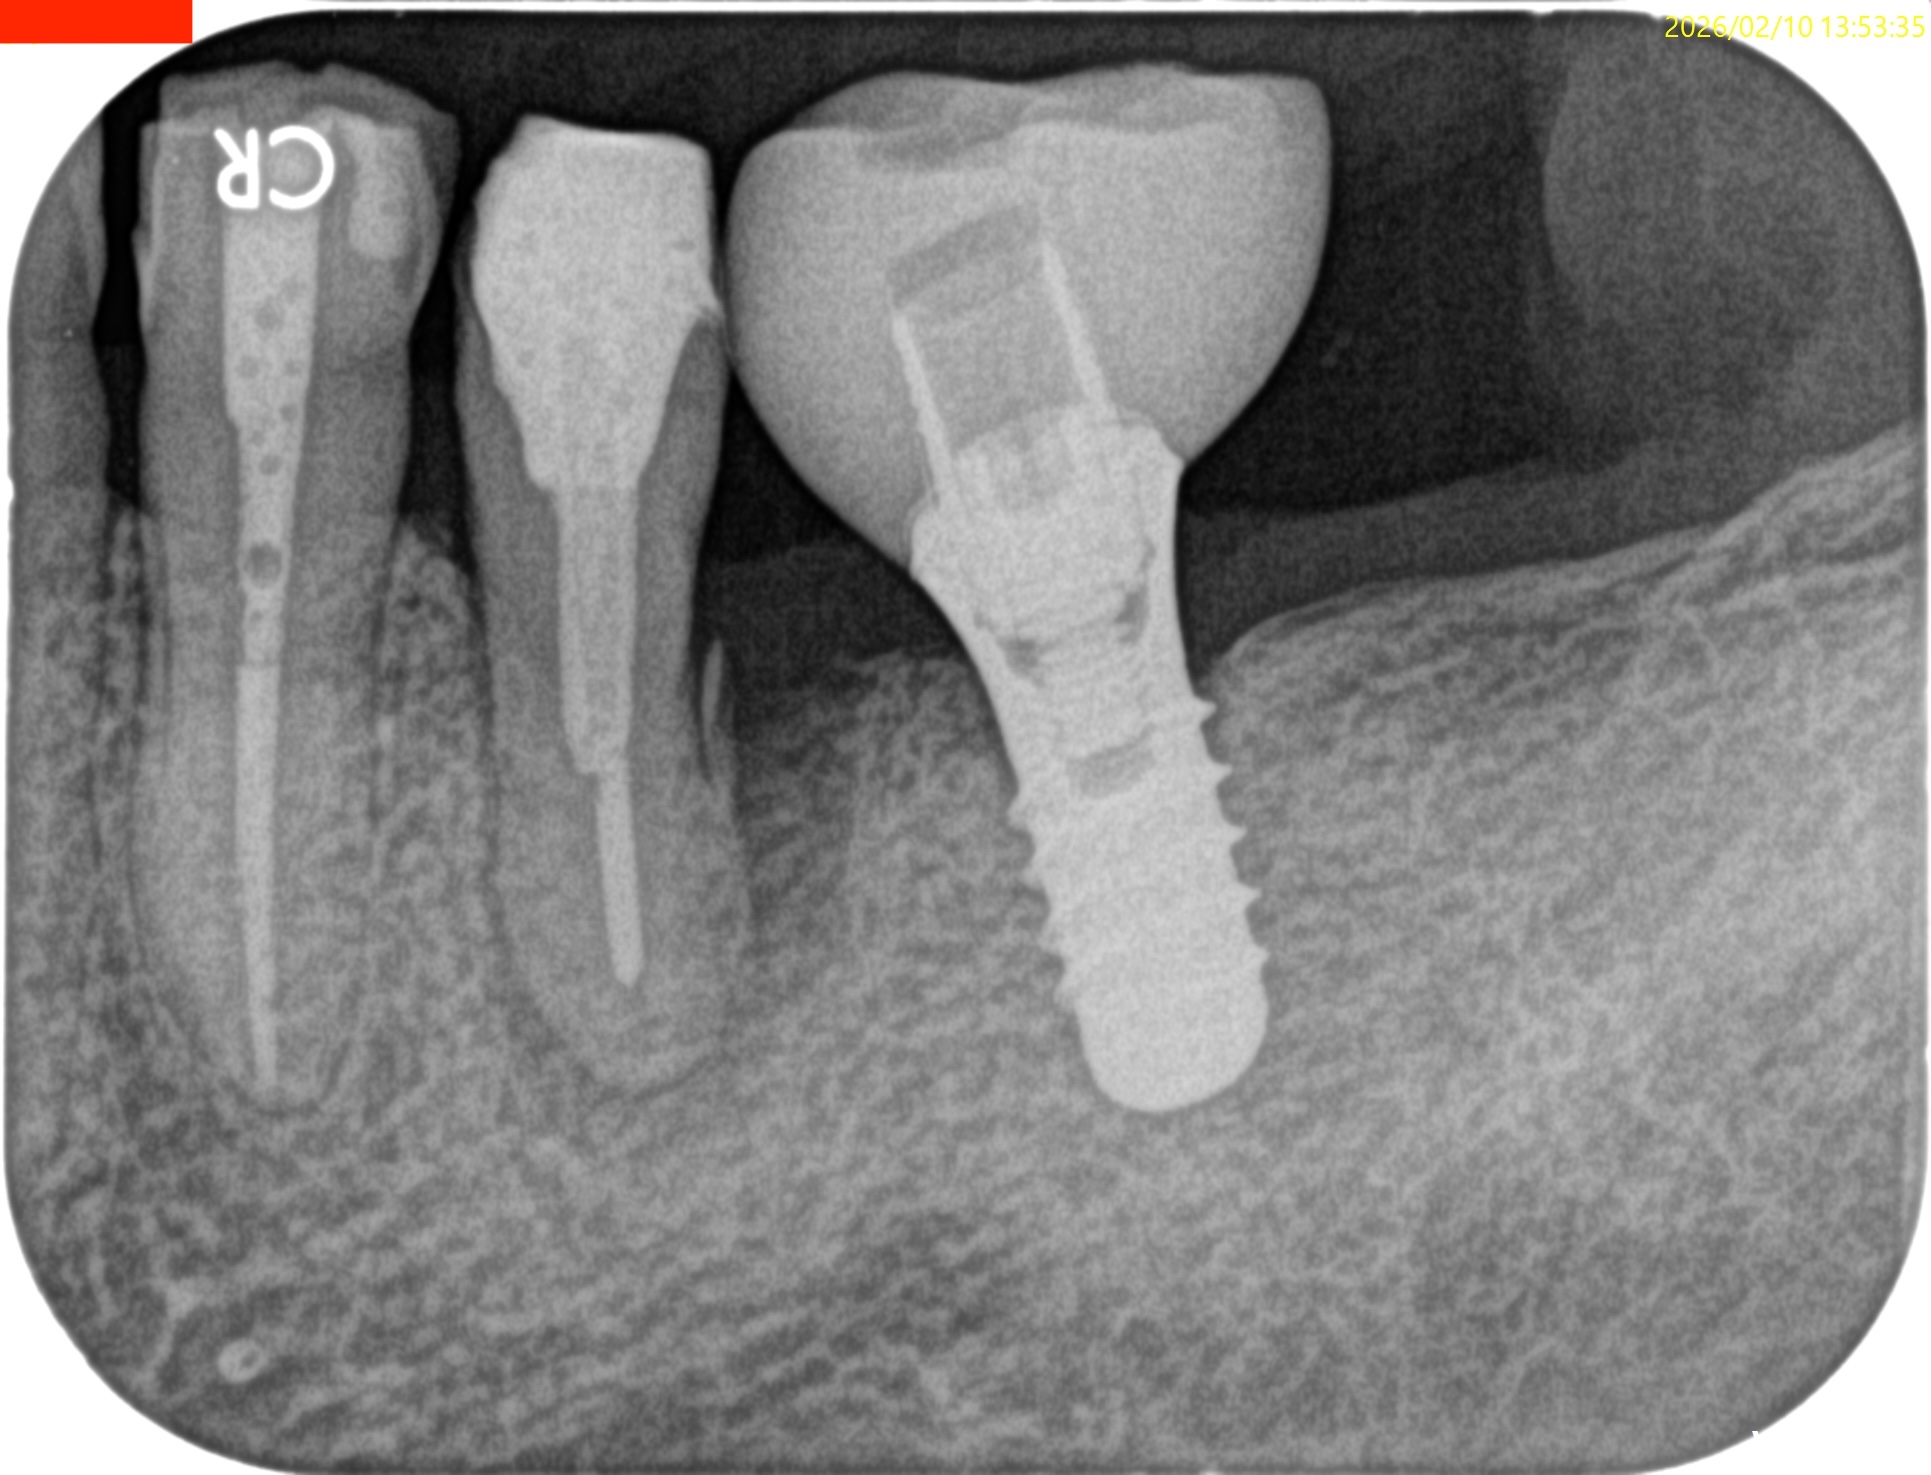

Pre-op Endo test(2026.2.10)

術後にPA, CBCTを撮影した。